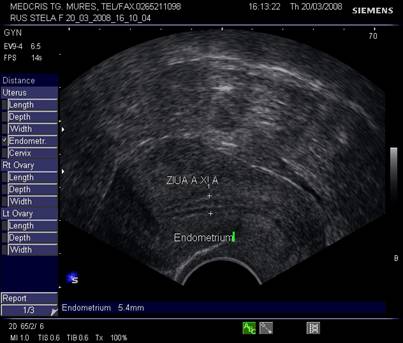

Endometrul - grosimea sa este apreciata in sectiune longitudinala. Masurarea se va face de la interfata miometru - endometru la interfata identica, opusa, de pe peretele celalat uterin. Maxim acceptat normal este de 1,5 cm in perioada de premenopauza.[5] Postmenopauza in mod normal nu depaseste 5 mm, de obicei este atrofic si apare ca o imagine ecogena lineara. Daca apare o colectie anecogena postmenopauzala intrauterina, prin atrofie cervicala, aceasta colectie nu trebuie sa fie masurata la calculul grosimii endometriale.[2,6]

Grosimea endometrului este de circa 1-2 mm la inceput de faza proliferativa, de cca 5 mm in ziua 10 -11, cu 1 zi preovulator cca 10 - 12 mm,apoi stagneaza, toate acestea la un ciclu menstrual de 28 zile.[2,6]

Fig nr.362. Endometru in faza de secretie tardiva ( Ziua a XI a de ciclu menstrual ). Se remarca linia continua dintre cele doua ecostructuri endometriale de pe peretii uterini opusi .

Fig. Nr.364.Endometru de faza secretorie medie, cu pierderea interliniei caracteristica fazei de proliferare